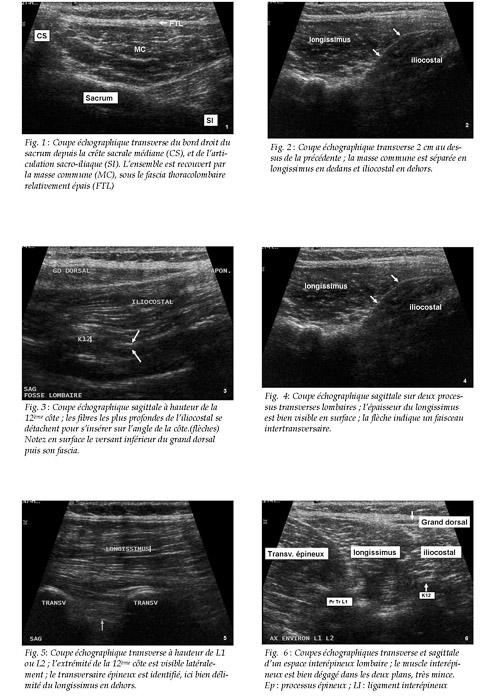

Gel Contact N°17

JUIN 2008